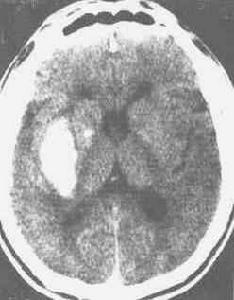

6.Leigh病臨床少見在兒童後期或成年時逐漸出現錐體外系肌強直CT顯示殼核空洞形成。